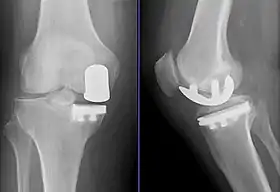

![]() تصوير بالأشعة of a knee arthroplasty of the medial compartment | |